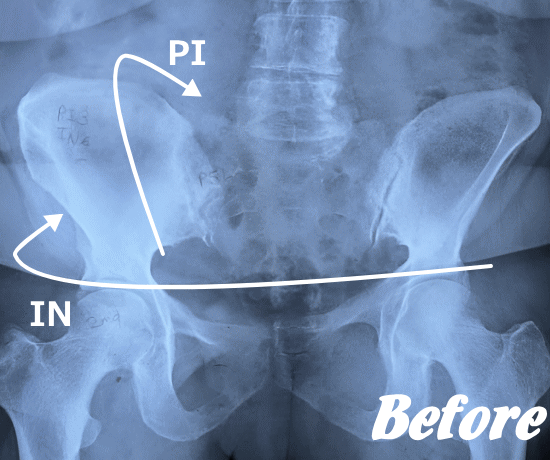

| 施術前 | 施術後 |

HALOカイロプラクティック☆平和島整体院では、梨状筋症候群の場合、多くは骨盤(仙腸関節)や股関節のズレにより、臀部の筋肉が緊張し、坐骨神経を圧迫していると考えます。

したがって、仙腸関節、股関節、腰椎などを本来あるべき正しい位置へと戻すことで、圧迫を取り除き、痛みや痺れの解消を目指します。